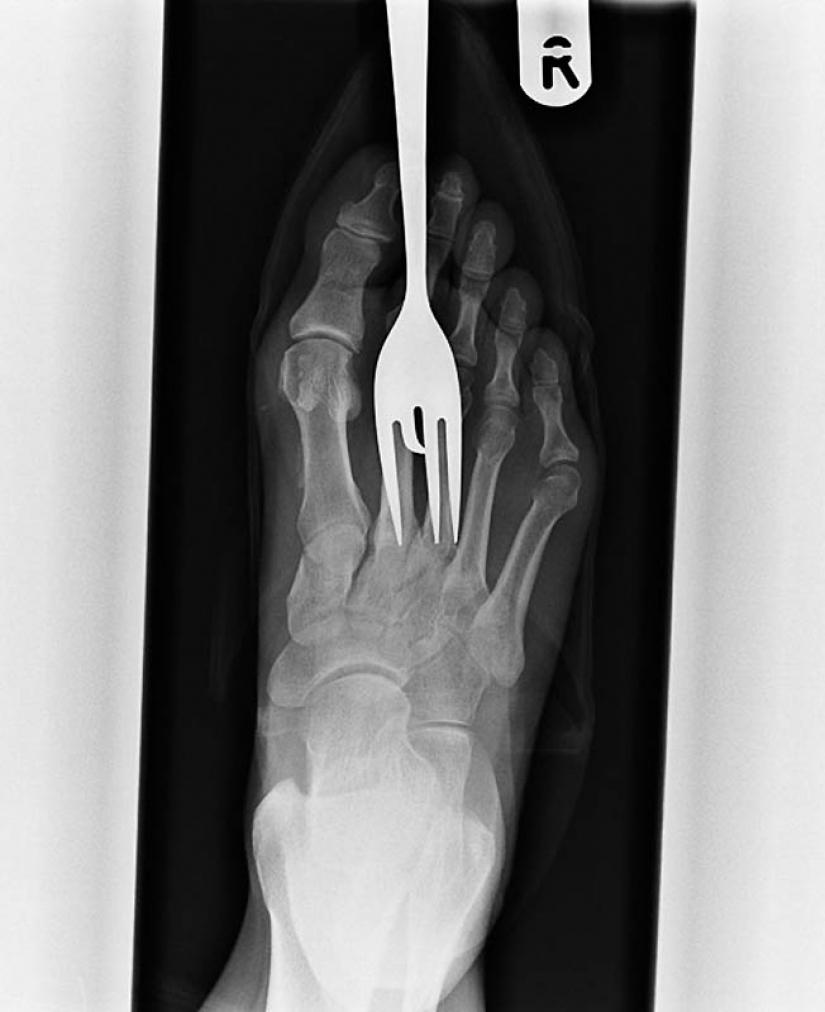

10. Another patient stepped on a fork.